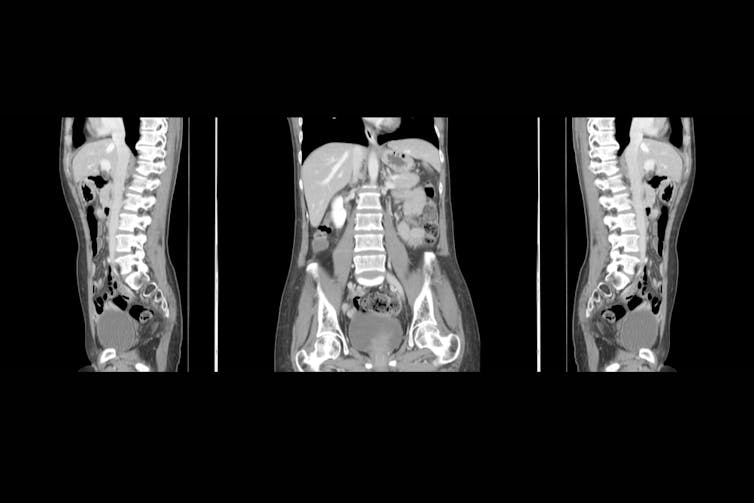

Computed tomography (CT)

This technique uses an x-ray beam to produce cross-sectional images of the human body. When the imaging process is taking place, the x-ray tube continuously emits an x-ray beam and is rotating in a 360 degree circle in a device called a gantry.

While this is happening, the patient is lying on a special CT imaging table that is allowing the x-ray beam through. The x-ray beam is shaped similar to a hand-held fan and is often described as a fan beam. There are multiple digital detectors located within this circular gantry that continually identify the energy of the x-ray photons that exit the patient.

The motion of the table and patient moving through the gantry allows images to be reconstructed as slices (or tomographs) of human tissue. The most common CT exam is to scan a patient’s chest, abdomen and pelvis, and the most common reason for this is to identify the spread of cancer. “X-ray dyes” are injected into patients to identify cancer when using CT imaging, as the cancer tissue will absorb the “x-ray dye” and be more obvious on the image.

With routine CT imaging techniques, there should not be any risks or danger to patients from the levels of radiation used.